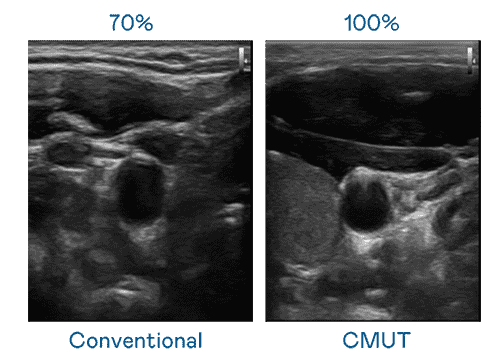

CMUT 技术是一种用电容式微机电元件来产生超音波讯号的技术。。与传统 PZT 压电式技术相比,,,CMUT 频宽增加 30%,,更宽频的超音波讯号让影像解析度大幅提升,,,,是实现高影像品质医疗超音波扫描、、、促进精准医疗发展的关键技术。。。

超音波影像的解析度高低,,首先取决于探头能发出的讯号频宽。。。。口袋牛店 CMUT 可提供高清晰的超音波讯号,,提供高频宽、、、、高灵敏度、、影像纹理细节更高的超音波影像,,协助医护人员缩短影像判读时间及利用精准的医疗影像进行诊断。。。